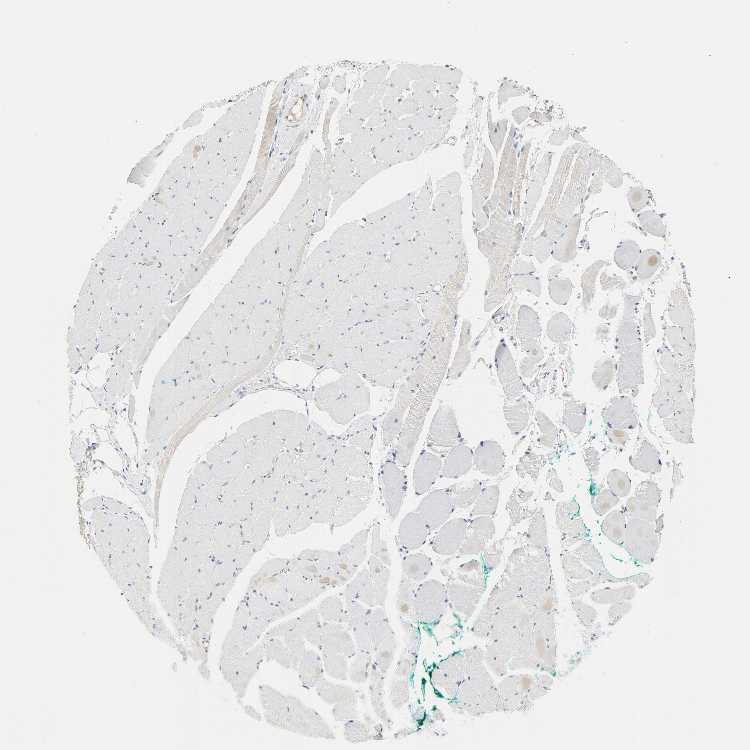

SKELETAL MUSCLE - Antibody stainingi

Antibody staining in the annotated cell types in the current human tissue is reported as not detected, low, medium, or high, based on conventional immunohistochemistry profiling in selected tissues. This score is based on the combination of the staining intensity and fraction of stained cells.

Each image is clickable and will lead to virtual microscopy that enables deeper exploration of all samples and also displays staining intensity scores, fraction scores and subcellular localization as well as patient and tissue information for each sample.

Antibody HPA051798Antibody CAB004639

Myocytes Not detectedNot detected